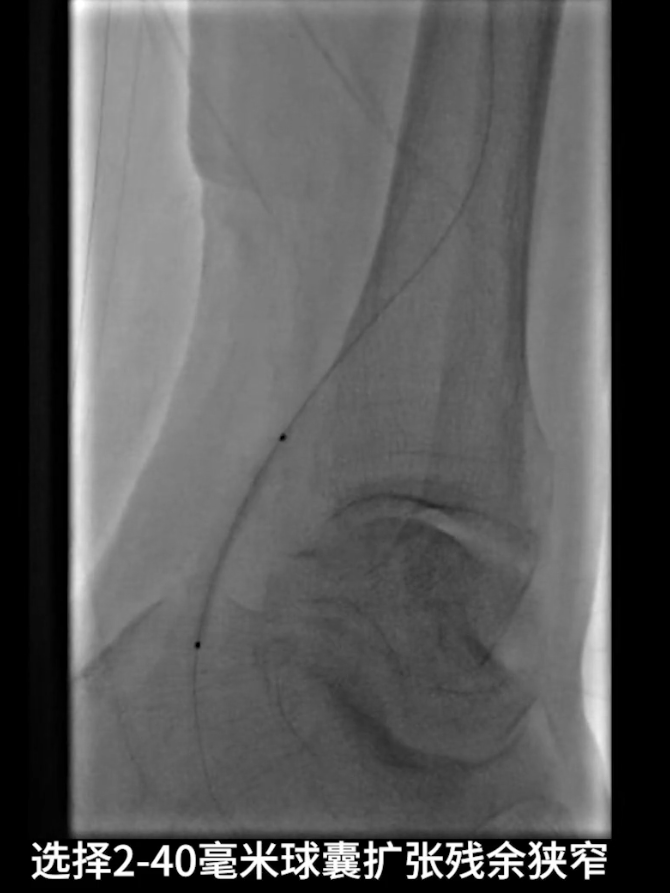

更换0.014系统导丝,经交通支选入胫后动脉远端,

再以2.0×40mm球囊扩张残余狭窄,并压迫远端逆行穿刺点止血,确保膝下流出道通畅。